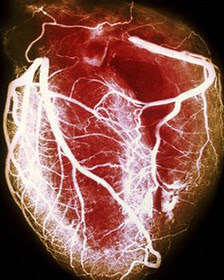

Tiene un corazón mayor de lo usual por una condición médica conocida como cardiomiopatía hipertrófica (HCM). Los que la sufren tienen las paredes de este músculo vital más gruesas, por lo que su corazón es más duro y de gran tamaño, algo que implica un mayor riesgo de muerte súbita.

Cada año, explica, hay entre un 2-3% de posibilidades de que su corazón pare de latir. El riesgo es acumulativo y a medida que pasan los años mayor es el riesgo de que su problema sea fatal.

La ciencia médica es hoy capaz de minimizar esta amenaza gracias al implante de un desfibrilador, capaz de emitir un impulso eléctrico que reanime su corazón si éste decide pararse.